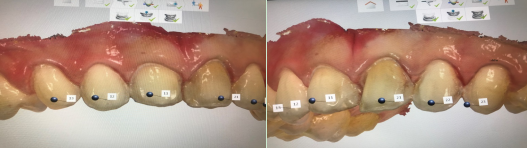

患者,女,20岁。主诉:“因对牙齿颜色及形态不满意,要求修复。”

治疗过程

瓷贴面通过酸蚀粘接在完好的、预备过的釉质上,具有更好的粘接强度、颜色稳定性和美观效果。

1、颜色美观,可较逼真地模仿天然性的形态结构、表面特征。

2、经氢氟酸酸蚀后的瓷贴面粘接强度相对较其他贴面系统强。

3、高磨光性的全瓷表面不利于菌斑附着,有利于牙龈健康。

4、边缘的密合性佳,有利于减少牙龈刺激和边缘微漏。

5、烤瓷内在强度高,抗磨耗和磨损能力较树脂强。

6、色泽稳定性佳,不会吸水膨胀,边缘微漏或染色较树脂轻。